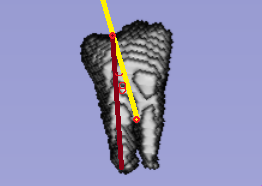

本项目基于先进的口腔CBCT影像数据,结合人工智能深度学习算法, 提出了一种基于口腔CBCT影像的牙齿牙根角度三维智能测量方法。该方法可实现从口腔CBCT图像中准确、稳定且全自动地测量出每颗牙齿的临床牙根角度三维测量值,这些测量值在口腔正畸手术中 具有十分重要的临床指导意义。从三维空间自动智能地计算出牙齿牙根角度测量值,三维测量值较之当前临床常规测量具有更高的准确度以及实现了测量的全自动化。该软件技术的开发对于口腔正畸手术具有极高的指导意义和临床价值。